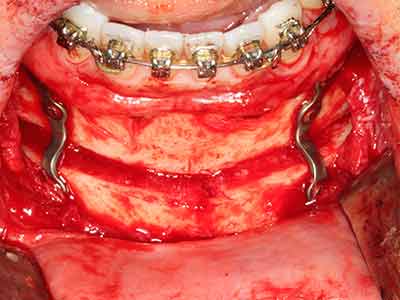

As shown in the past, basically any bone surgery procedure represents a possible indication for piezo surgery. Thus preparation of the mobile segment in distraction osteogenesis (Fig. 23-25) and sandwich osteotomy uses special attachments without endangering the blood supply to the crestal section, which is essential for the success of both techniques (Gonzalez-Garcia, Diniz-Freitas et al. 2008).

Purely orthodontic indications include orthognathic surgery, genioplasty (Fig. 27-30) and orbital decompression in patients with advanced endocrine orbitopathy as a result of Basedow’s disease (Ponto, Zwiener et al. 2014). Piezo devices are also used in maxillofacial surgery and to remove tumours at the base of the skull in various hospitals.